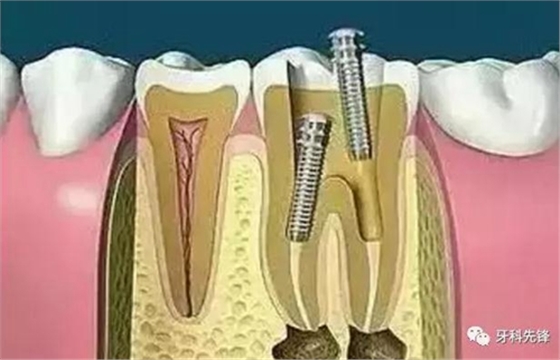

根管治療(root canal therapy)是牙髓病和根尖周病的國際上最常用的有效治療方法。根管治療術(shù)的原理是通過機(jī)械和化學(xué)方法去除根管內(nèi)的大部分感染物,并通過充填根管、封閉冠部,防止發(fā)生根尖周病變或促進(jìn)已經(jīng)發(fā)生的根尖周病變的愈合。

7、根管打樁

因牙體缺損過多,導(dǎo)致牙的強(qiáng)度(承受力量的性能)大幅度下降,不能很好地承受咀嚼力量。打樁的目的是增加牙根及牙冠的強(qiáng)度,增加患牙的穩(wěn)固。